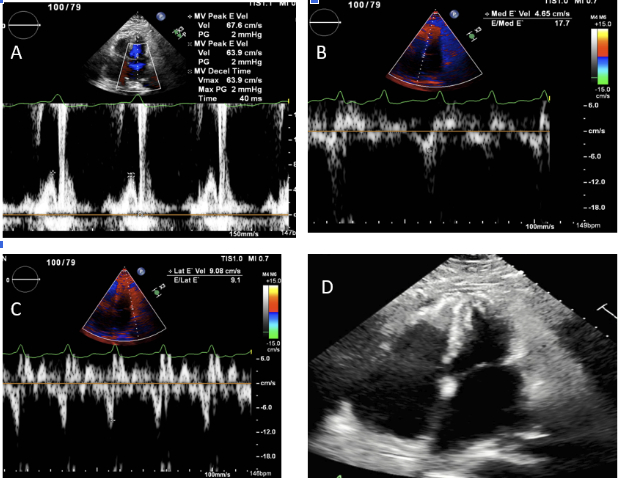

On admission, echocardiography revealed severe right atrial enlargement and grade III diastolic dysfunction. Attempts at rate and rhythm control with multiple agents were unsuccessful. On day 2 of admission, he developed cardiogenic shock (CI 1.5, RA 20, PCWP 40, PA 50/30 [mPA 40], PVR 3, CPO 0.53, PAPI 1.0), necessitating V-A extracorporeal membrane oxygenation and Impella CP for circulatory support.